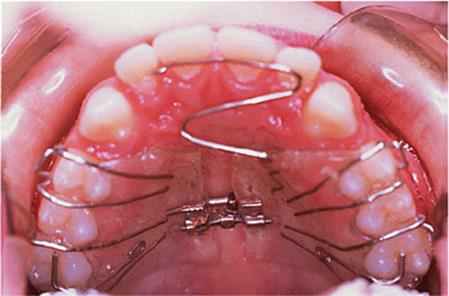

The appliance holds the mandible in a forward postured position, in this case with the incisors edge to edge (Fig. 18.1(f)). The facial musculature is thus stretched, and applies a posterior force to the upper arch and an anterior force to the lower arch. The lower incisors have acrylic capping to prevent excessive labial tilting of the lower incisors, and this also serves as a bite-plane to reduce the overbite (Chapter 10). The appliance must be worn for at least 14–16 hours each day, but once the overjet has been reduced fully the amount of daily wear can gradually be reduced to sleeping hours only. The patient should continue to wear the appliance overnight in this way as a retainer, at least until the period of rapid pubertal growth is complete. Figures 18.1(g) and 18.1(h) show the dental and facial changes which occurred during treatment.

Fig. 18.1. (a) This 12-year-old girl had a skeletal II facial pattern and average facial proportions. The lips were incompetent with the lower lip lying below the upper incisors at rest. (b), (c) She had a Class II division 1 malocclusion with an overjet of 10 mm, the overbite was increased and complete, and the molar relationship was Class II on both sides. (d), (e) The upper and lower arches were well aligned. (f) A functional appliance (an activator) was fitted. (g) The corrected occlusion with Class I incisor and molar relationships. (h) The patient's facial profile at the end of treatment.

18.5.1. The Andresen activator

There are many variations upon Andresen's original design. An Andresen activator is shown in Fig. 18.5. It is a monoblock design, that is to say it comprises upper and lower acrylic appliances fused together. The original design had a solid palate, but that shown has been made with an open palate to reduce its bulk. The lower incisors are capped to minimize the tendency for them to procline during overjet reduction, and which also serves as a bite-plane to reduce the overbite. The capping resists tipping of the teeth so that any labial movement will have to be bodily translation and is therefore minimized. The labial bow lies passively against the upper incisors, and the palatal wire is again intended to minimize palatal tilting of the upper incisors.

Fig. 18.5. Andresen activator used to treat the patient shown in Fig. 18.1.